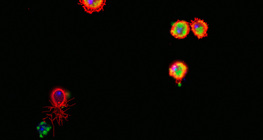

100-szoros nagyítás

400-szoros nagyítás

20-szoros nagyítás

Boglárka, 150-szeres nagyítás

Spárga, 100-szoros nagyítás

Kukorica, 150-szeres nagyítás

200-szoros nagyítás

2000-szeres nagyítás

600-szoros nagyítás